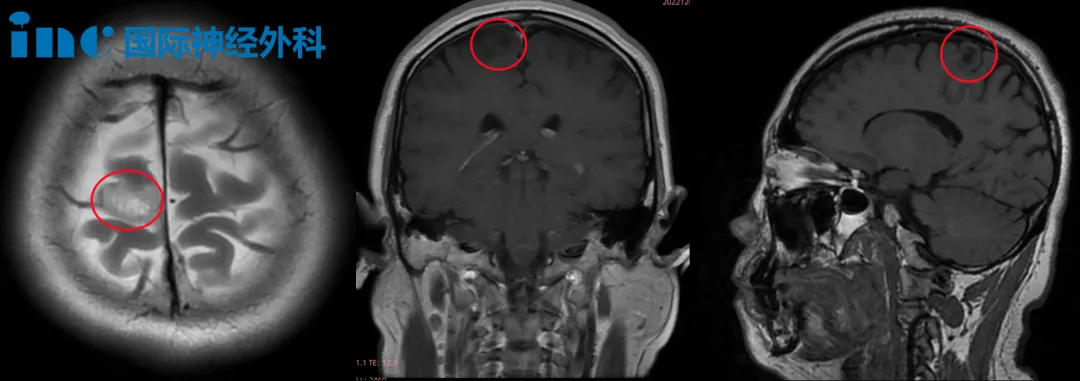

41岁女性患者莫女士分享其右额叶低级胶质瘤的完整诊疗经历。2022年11月3日,患者在办公室工作期间突发癫痫发作,出现明显抽搐症状及意识丧失,经紧急送医救治。后续医学检查确诊为右额叶低级胶质瘤,影像学显示肿瘤位置紧邻运动功能区,存在压迫重要脑组织导致运动功能缺损的潜在风险。

当地医院完成初步检查后,医疗团队建议采取保守治疗方案,并明确告知开颅手术可能带来瘫痪等严重并发症风险。通过友人推荐,患者了解到INC巴特朗菲教授在类似病例中的丰富经验,于2022年11月29日安排远程专家会诊。巴特朗菲教授详细评估病情后,建议尽早进行手术治疗,患者在一个月内完成全部术前准备并安排手术。